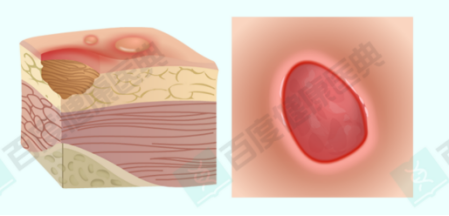

重点科普二:空洞型褥疮——“外小内大”的隐形溃烂,处理不当必致恶化

除了黑痂型褥疮,空洞型褥疮也是临床中非常常见的特殊类型,它同样隐蔽且危险,很多家属直到病情严重才发现,此时往

往已错过*佳治疗时机。

空洞型褥疮的典型特点是“外小内大”:疮口看起来很小,但皮下或深部组织已经形成了巨大的空腔,就像一个“暗洞”,因此得

名空洞型褥疮。这种褥疮的形成,大多与不当处理(尤其是盲目干燥、结痂)有关——疮口表面愈合,但其内部的创面和空腔

并未愈合,形成暗洞,导致坏死组织、脓液无法排出,持续侵蚀深部组织。